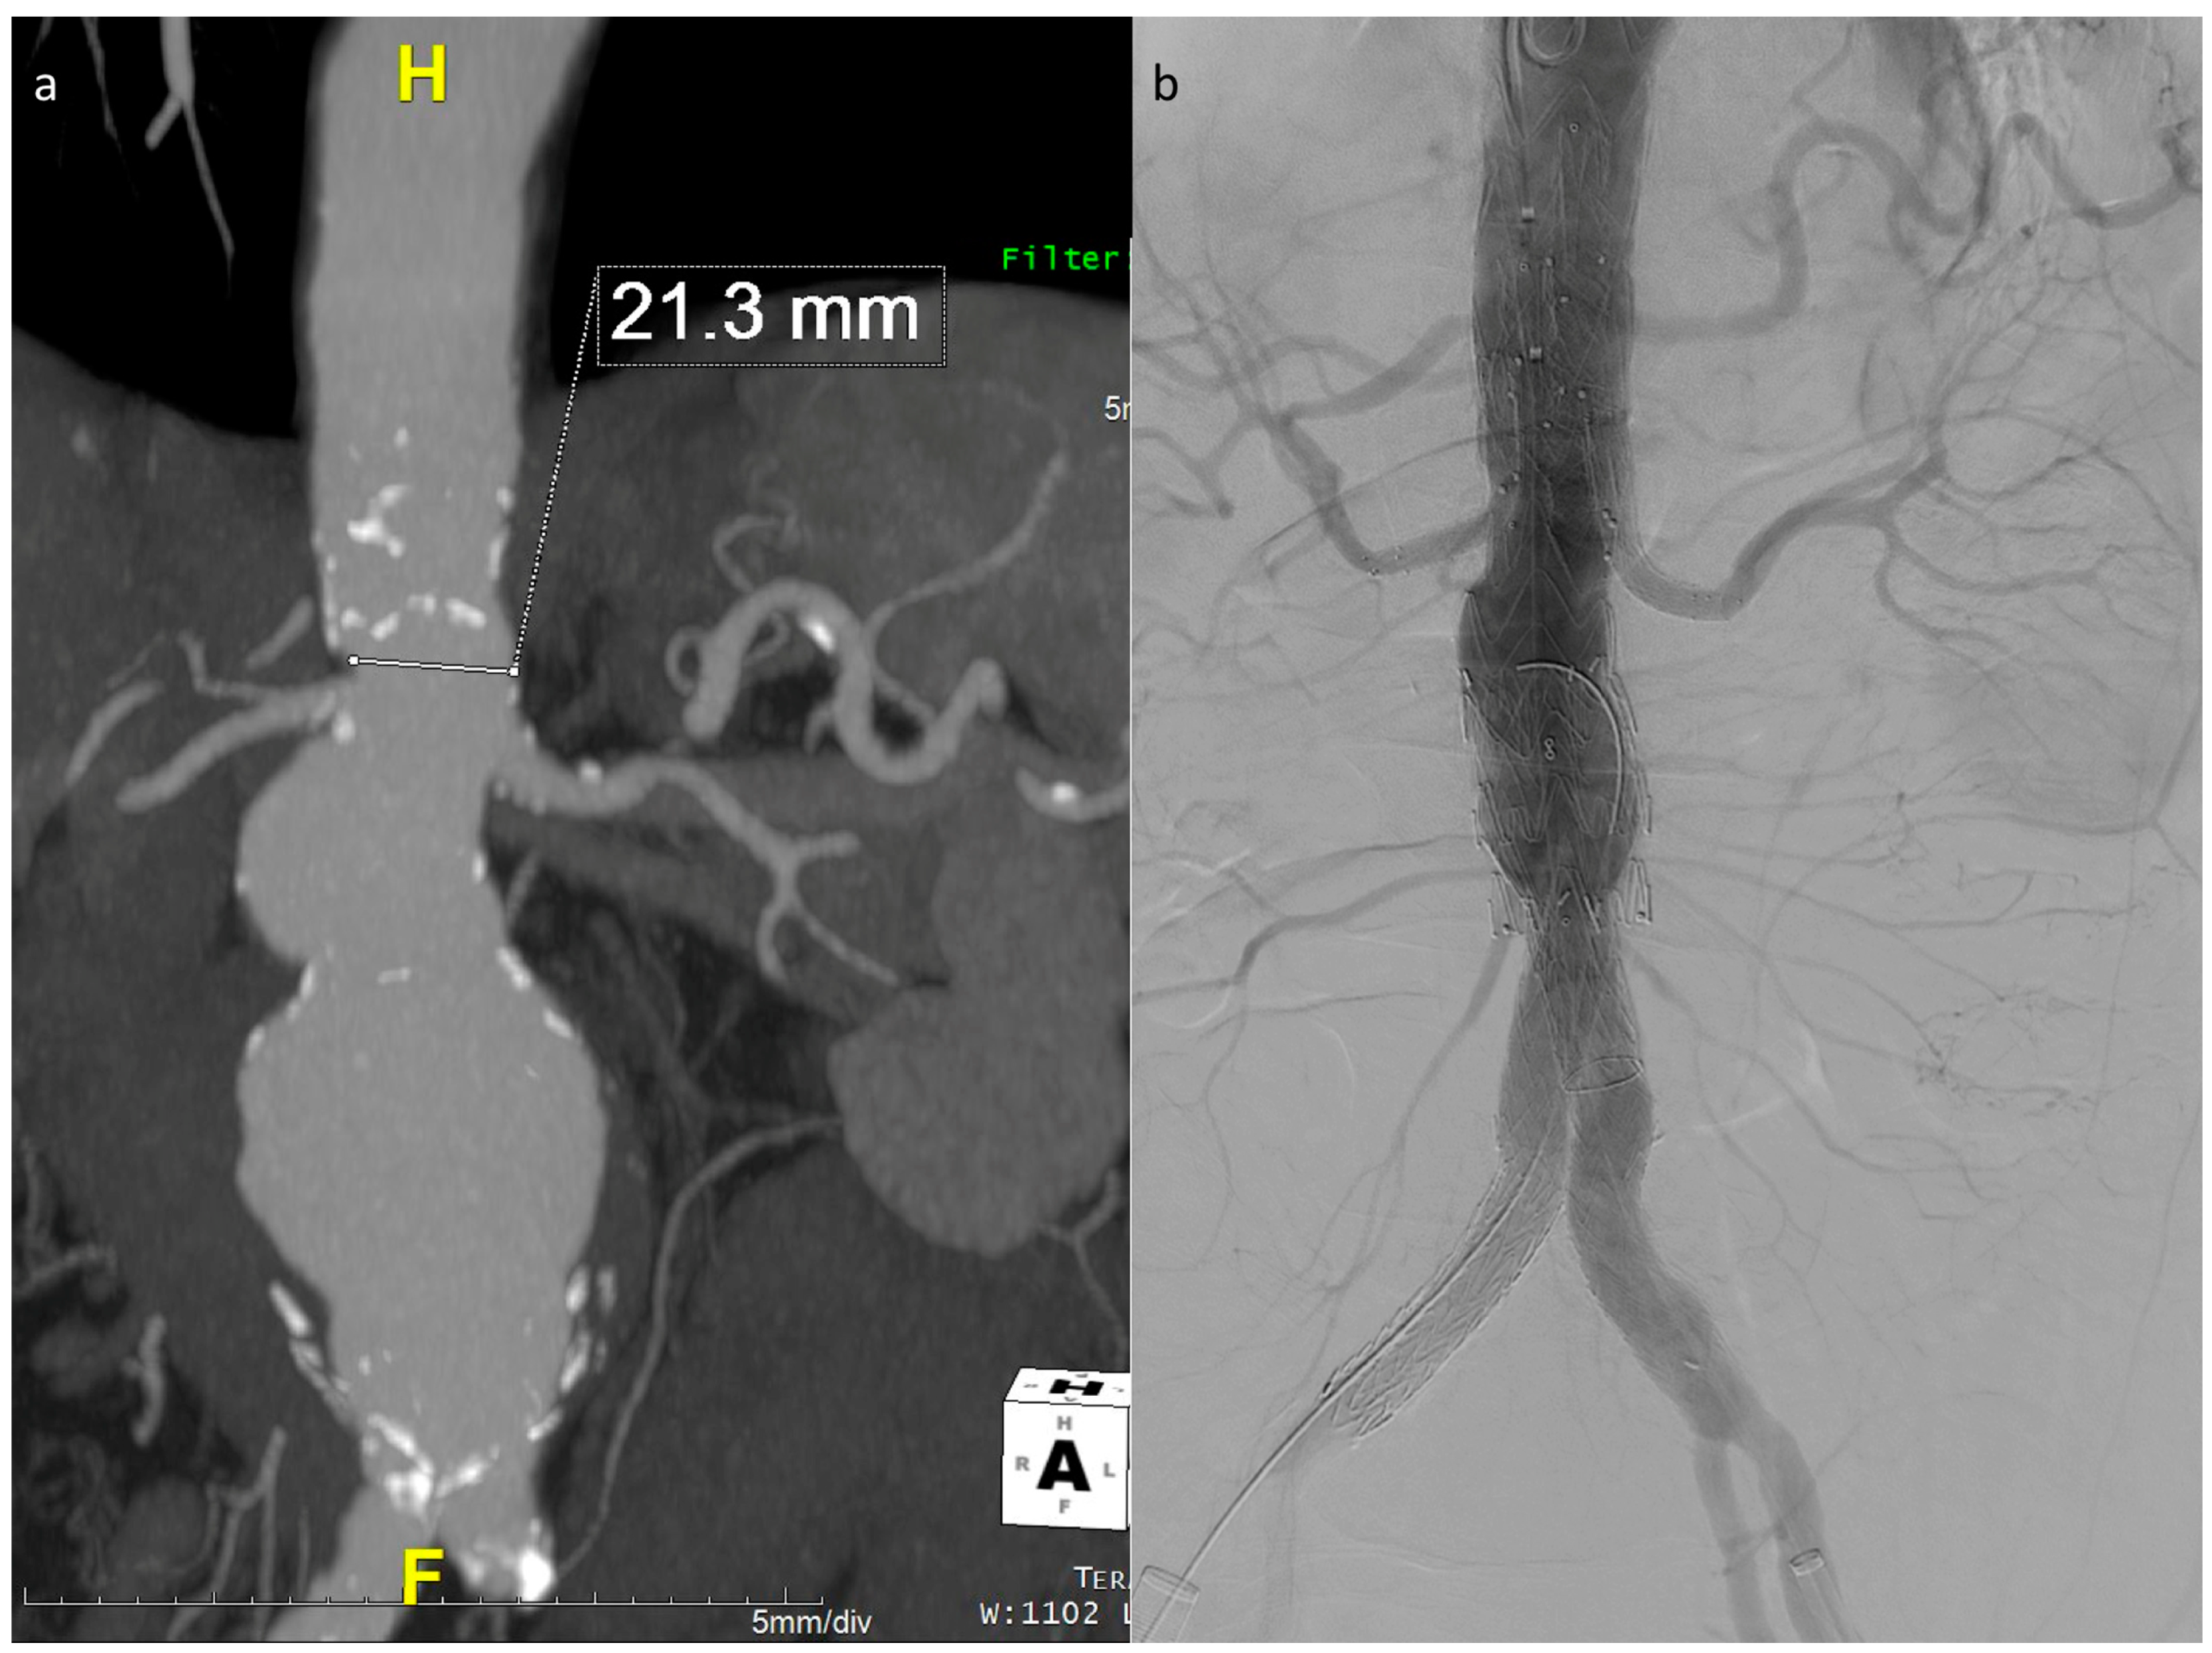

Preventing the distal end of the graft from fully expanding simplifies visceral vessel cannulation maneuvers and bridging component advancement, especially when dealing with restricted lumina (Figure 2). This aspect is even more critical when using an E-nside graft compared to outer-branched devices, given that while the middle portion of the endoprosthesis measures 24 mm in diameter, its distal segment re-expands to 26 or 30 mm with a reverse tapering. The partial deployment approach prevents this distal segment from filling up the inner aortic lumen at the renal artery ostia, a condition dependent on the graft deployment height, potentially leading to target vessel occlusion.

The described technique was used in 26 out of the 40 E-nside cases performed in the two authors’ institutions from January 2020 to March 2024, enabling the treatment of anatomies with an inner aortic lumen down to 20 mm in diameter (Figure 3).

Figure 3. Maximum intensity projection coronal view of the example case in Figure 1, showing a very narrow lumen just above the origin of the renals in a patient with a wide pararenal aneurysm (a). Final angiographic control (b).